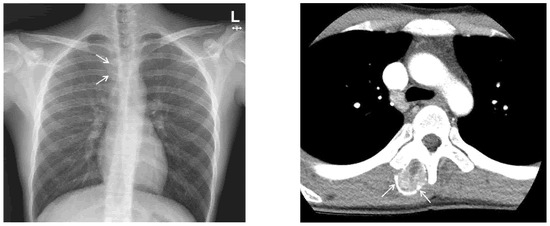

Chest X-ray images showed a radiopaque mass with rim calcification at the T4/5 paraspinal area (Figure 2). Computed tomography images revealed an approximately 2.8 × 2.5 cm wide, 4.5 cm high oval-shaped mass in the right paraspinal muscle with peripheral rim calcification (Figure 2) that was not seen on computed tomography images 5 months prior. The cleft between the mass and the adjacent bone was visible. On magnetic resonance imaging (MRI), the mass showed a heterogeneous high signal intensity on T2WI, isointense to muscle on T1WI with a peripheral low signal intensity rim, and homogeneous enhancement. In addition, perilesional soft tissue edema at the adjacent muscle was also noted (Figure 3). With a history of suspicious trauma (extracorporeal shock wave therapy) and radiologic findings, myositis ossificans was the most suspected diagnosis.

Figure 2. (Left) Chest X-ray demonstrates radiopaque mass (arrows) with rim calcification in the T4/5 paraspinal area. (Right) Axial CT scan shows an oval-shaped mass with peripheral rim calcification (arrows) in the right paraspinal muscle.